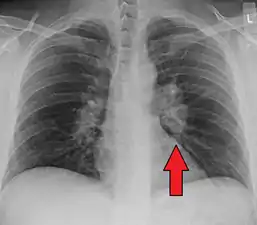

![]() | |

| Chest X-ray showing the typical nodularity of sarcoidosis, predominantly in the bases of the lungs. | |